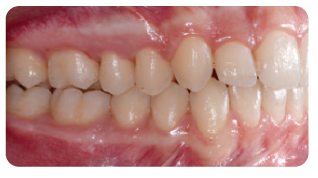

Overlay of initial (white) and post-treatment (green) occlusion in virtual setup viewer. Buccal grip points were planned on the upper right canine and first premolar, upper left canine and first molar, lower right first premolar, and lower left canine and second premolar. In addition, 0.1 mm of interproximal reduction (IPR) was planned at each contact point from the mesial surface of the upper right first molar to the mesial surface of the upper left first molar, and from the mesial surface of the lower left second premolar to the mesial surface of the lower right second premolar. IPR was used to reduce the proclination of both arches and achieve a good anterior relationship with normal overjet and overbite. Aligners were changed every two weeks. After the 12th planned set of aligners, four more were added to the series to refine the result (pictures below).

The clear aligner therapy lasted eight months. Treatment Results Post-treatment records indicated a satisfactory outcome after four months of Carriere Motion Appliance with fulltime Class II elastic wear and eight months of clear aligner therapy.

The patient showed an aesthetic profile and incisor display on smiling, along with a Class I canine and molar relationship. The midlines were centered and the crowding was resolved, but the second molar occlusal contacts were less than optimal, probably because of the presence of a palatal precontact. Post-treatment panoramic radiography evidenced good root parallelism with no sign of crestal bone height reduction or apical root resorption. Cephalometric analysis indicated that the inclination of the lower incisors with respect to the mandibular plane (IMPA) increased slightly, from 96.3° to 9.9°, demonstrating the anchorage control provided by the appliance (check Table 1 in the full article). Superimposition of the pre- and post-treatment cephalometric tracings, according to the method developed by Björk,9,10 highlighted a clockwise rotation of the occlusal plane. The appliance’s control of the vertical height and lower-incisor proclination was clear from the regional superimpositions. Even though the treatment period was short, the superimpositions revealed considerable residual growth in a downward and forward direction, since the initial radiographs were taken six months before treatment began.